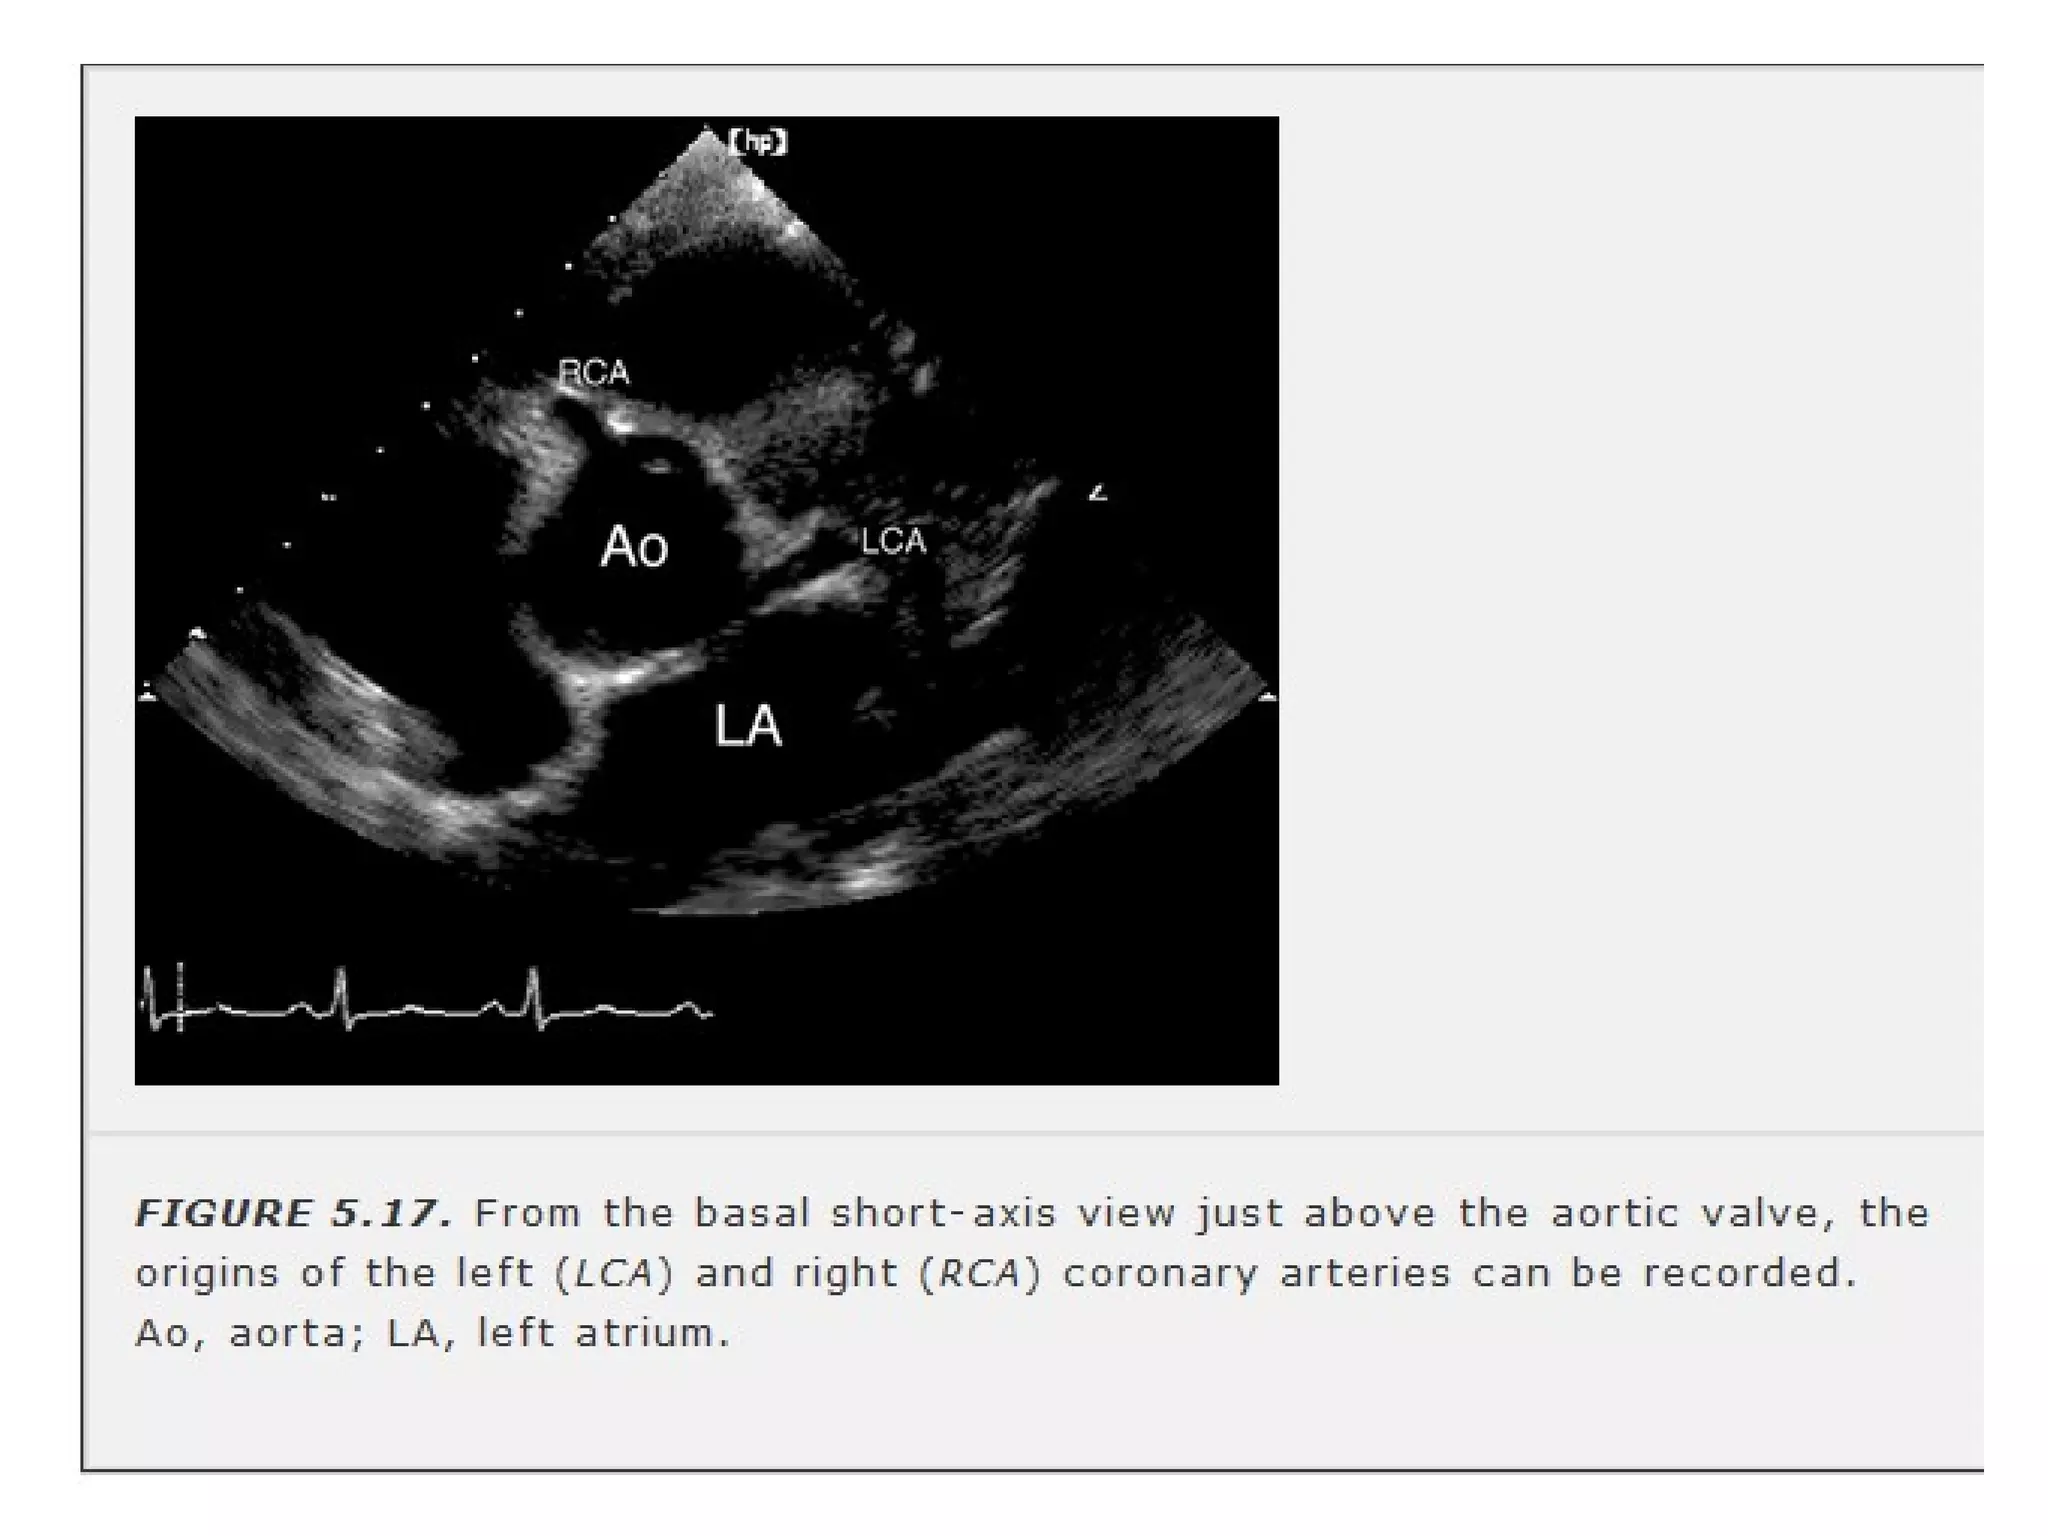

-Basal level- aortic annulus, AV, coronory

ostia, LA, TV, RVOT, PV & prox pa.

-annulus

regarded as clock face- LMCA at 4 & RCA

at 11